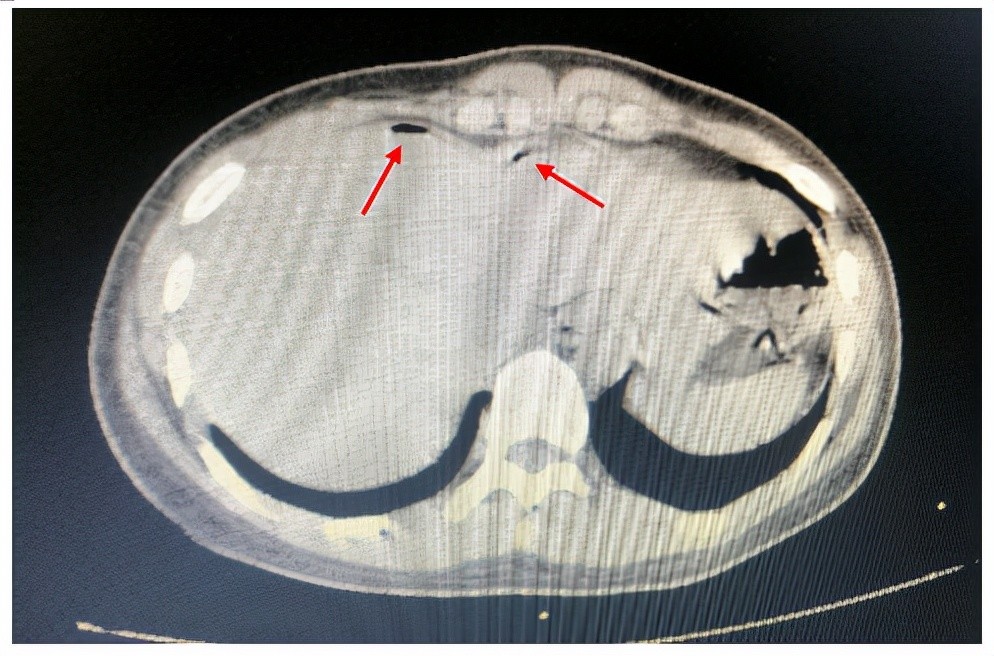

消化道穿孔影像图片,消化道穿孔图片

看到这张腹部平片第一诊断是什么呢?隔下游离气体-消化道穿孔啊!

消化道穿孔的ct诊断

消化道穿孔典型ct图片